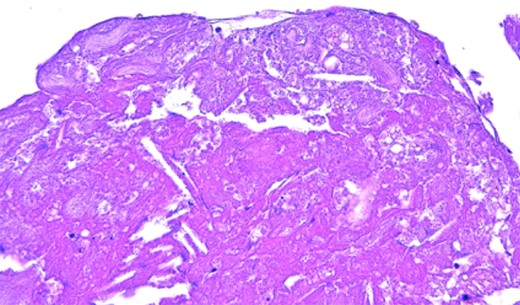

Patient resumed oral feeding on the first day after operation, and TEVAR using Zenith alpha (Cook, Bloomington, USA) for descending aortic aneurysm was performed on the 28th day. The patient was discharged by Day 59 post-surgery with no complication, and there was no recurrence of abdominal symptoms or findings suggestive of intestinal ischemia throughout the course. The white material collected intraoperatively was found to be cholesterol crystals as a result of the pathological test (Fig. 3).